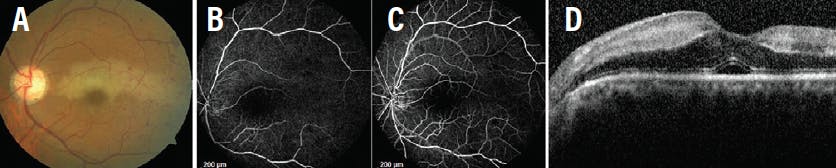

A 46-year-old hypertensive man presented with blurred vision in the right eye for 15 days. BCVA was 20/40 OD. Fundus examination revealed evidence of a nonischemic central retinal vein occlusion (CRVO) and a well-defined grayish-white lesion inferotemporal to the fovea (Figure 3A). FA showed inferior extension of the foveal avascular zone. OCT showed cystic changes with a hyperreflective band at the level of the IPL (Figure 3B). OCTA revealed capillary abnormalities in both the DCP and SCP inferior to the fovea (Figures 3C and 3D). The patient received three intravitreal injections of ranibizumab (Lucentis, Genentech) at monthly intervals. After 6 months, fundus examination revealed the persistence of PAMM with cystoid macular edema (CME).

<p>Figure 3. The color fundus photo suggests nonischemic CRVO with PAMM inferotemporal to the fovea (A). SD-OCT shows cystic changes in the center with a hyperreflective band at the level of IPL (B). OCTA shows capillary abnormalities in both the DCP and SCP (C and D).</p>

Figure 3. The color fundus photo suggests nonischemic CRVO with PAMM inferotemporal to the fovea (A). SD-OCT shows cystic changes in the center with a hyperreflective band at the level of IPL (B). OCTA shows capillary abnormalities in both the DCP and SCP (C and D).